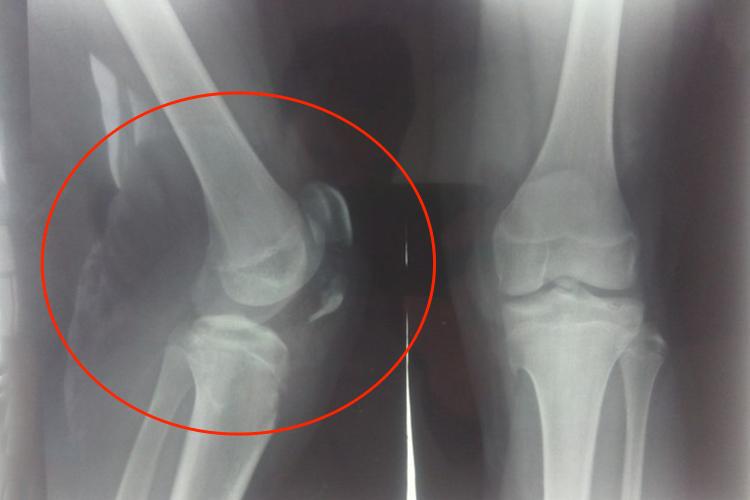

肿胀和压痛集中在胫骨近端前侧,可出现关节积液和积血。在胫骨近端和股骨髁之间的皮下可触及一游动性三角形骨块,骨块远端向前凸起、挤压皮肤。X线检查可见侧位上胫骨稍向内旋转,可出现一个平滑的、水平的、无移位的、射线可通过的骨折线穿过粗隆。

胫骨髁间嵴撕脱性骨折

表现为膝关节疼痛、肿胀、无法负重、屈伸活动受限。体格检查时可见膝关节肿胀、前后方稳定性降低,前抽屉试验和Lachman试验可为阳性。X线片可清楚显示髁间嵴骨折和移位。